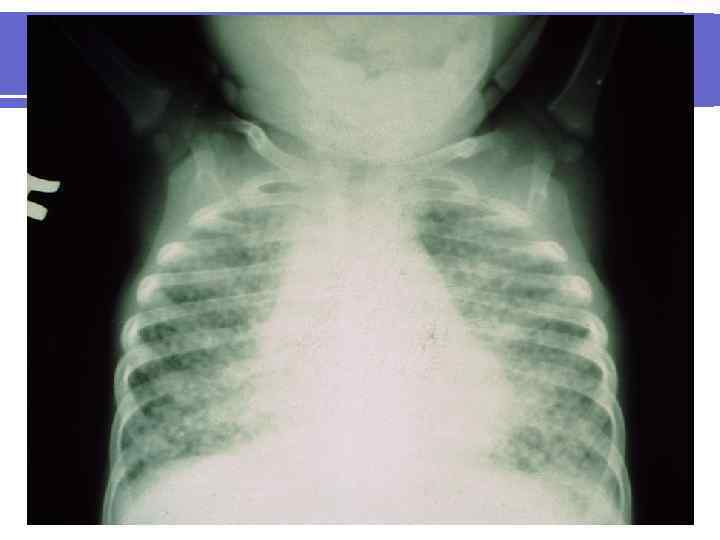

1. Пневмоцистная пневмония Клинические проявления: l Острое начало l Повышение температуры тела до 40 ◦C l Экспираторная одышка, сухой кашель, акроцианоз l Прогрессирующая дыхательная недостаточность (гипоксия всегда очень выражена) l На рентгенограмме ОГК - двусторонние инфильтраты, которые имеют вид «матового стекла» ( «ватная» рентгенограмма). l Возможна нормальная рентгенограмма или сетчатая перестройка легочного рисунка l Летальность достигает 40 -70%

l Chest x-ray of a child with Pneumocystis carinii l pneumonia demonstrating diffuse “ground glass” infiltrates.